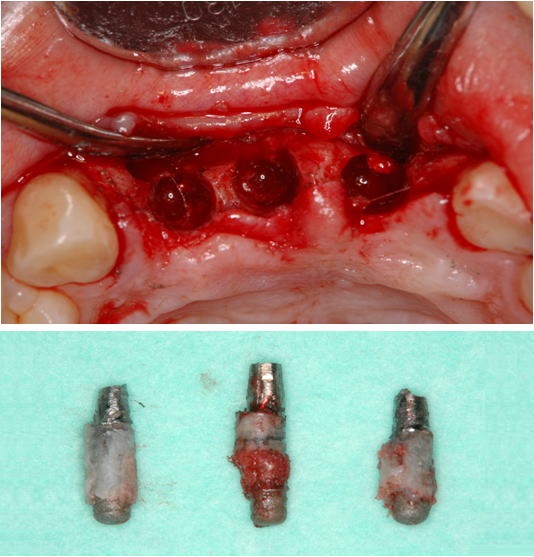

4.極度の骨・軟組織欠損がある2歯欠損症例

(他院でトラブルとなった症例 2の再インプラント治療、自家骨移植と有茎口蓋弁移植)

まず予後不良インプラント撤去し、極度の骨欠損があったが、オトガイ部から10mmの厚みの皮質海綿ブロック骨移植にて審美的インプラント治療を行いました。歯肉の厚みを増やすために有茎口蓋弁移植も併用しました。